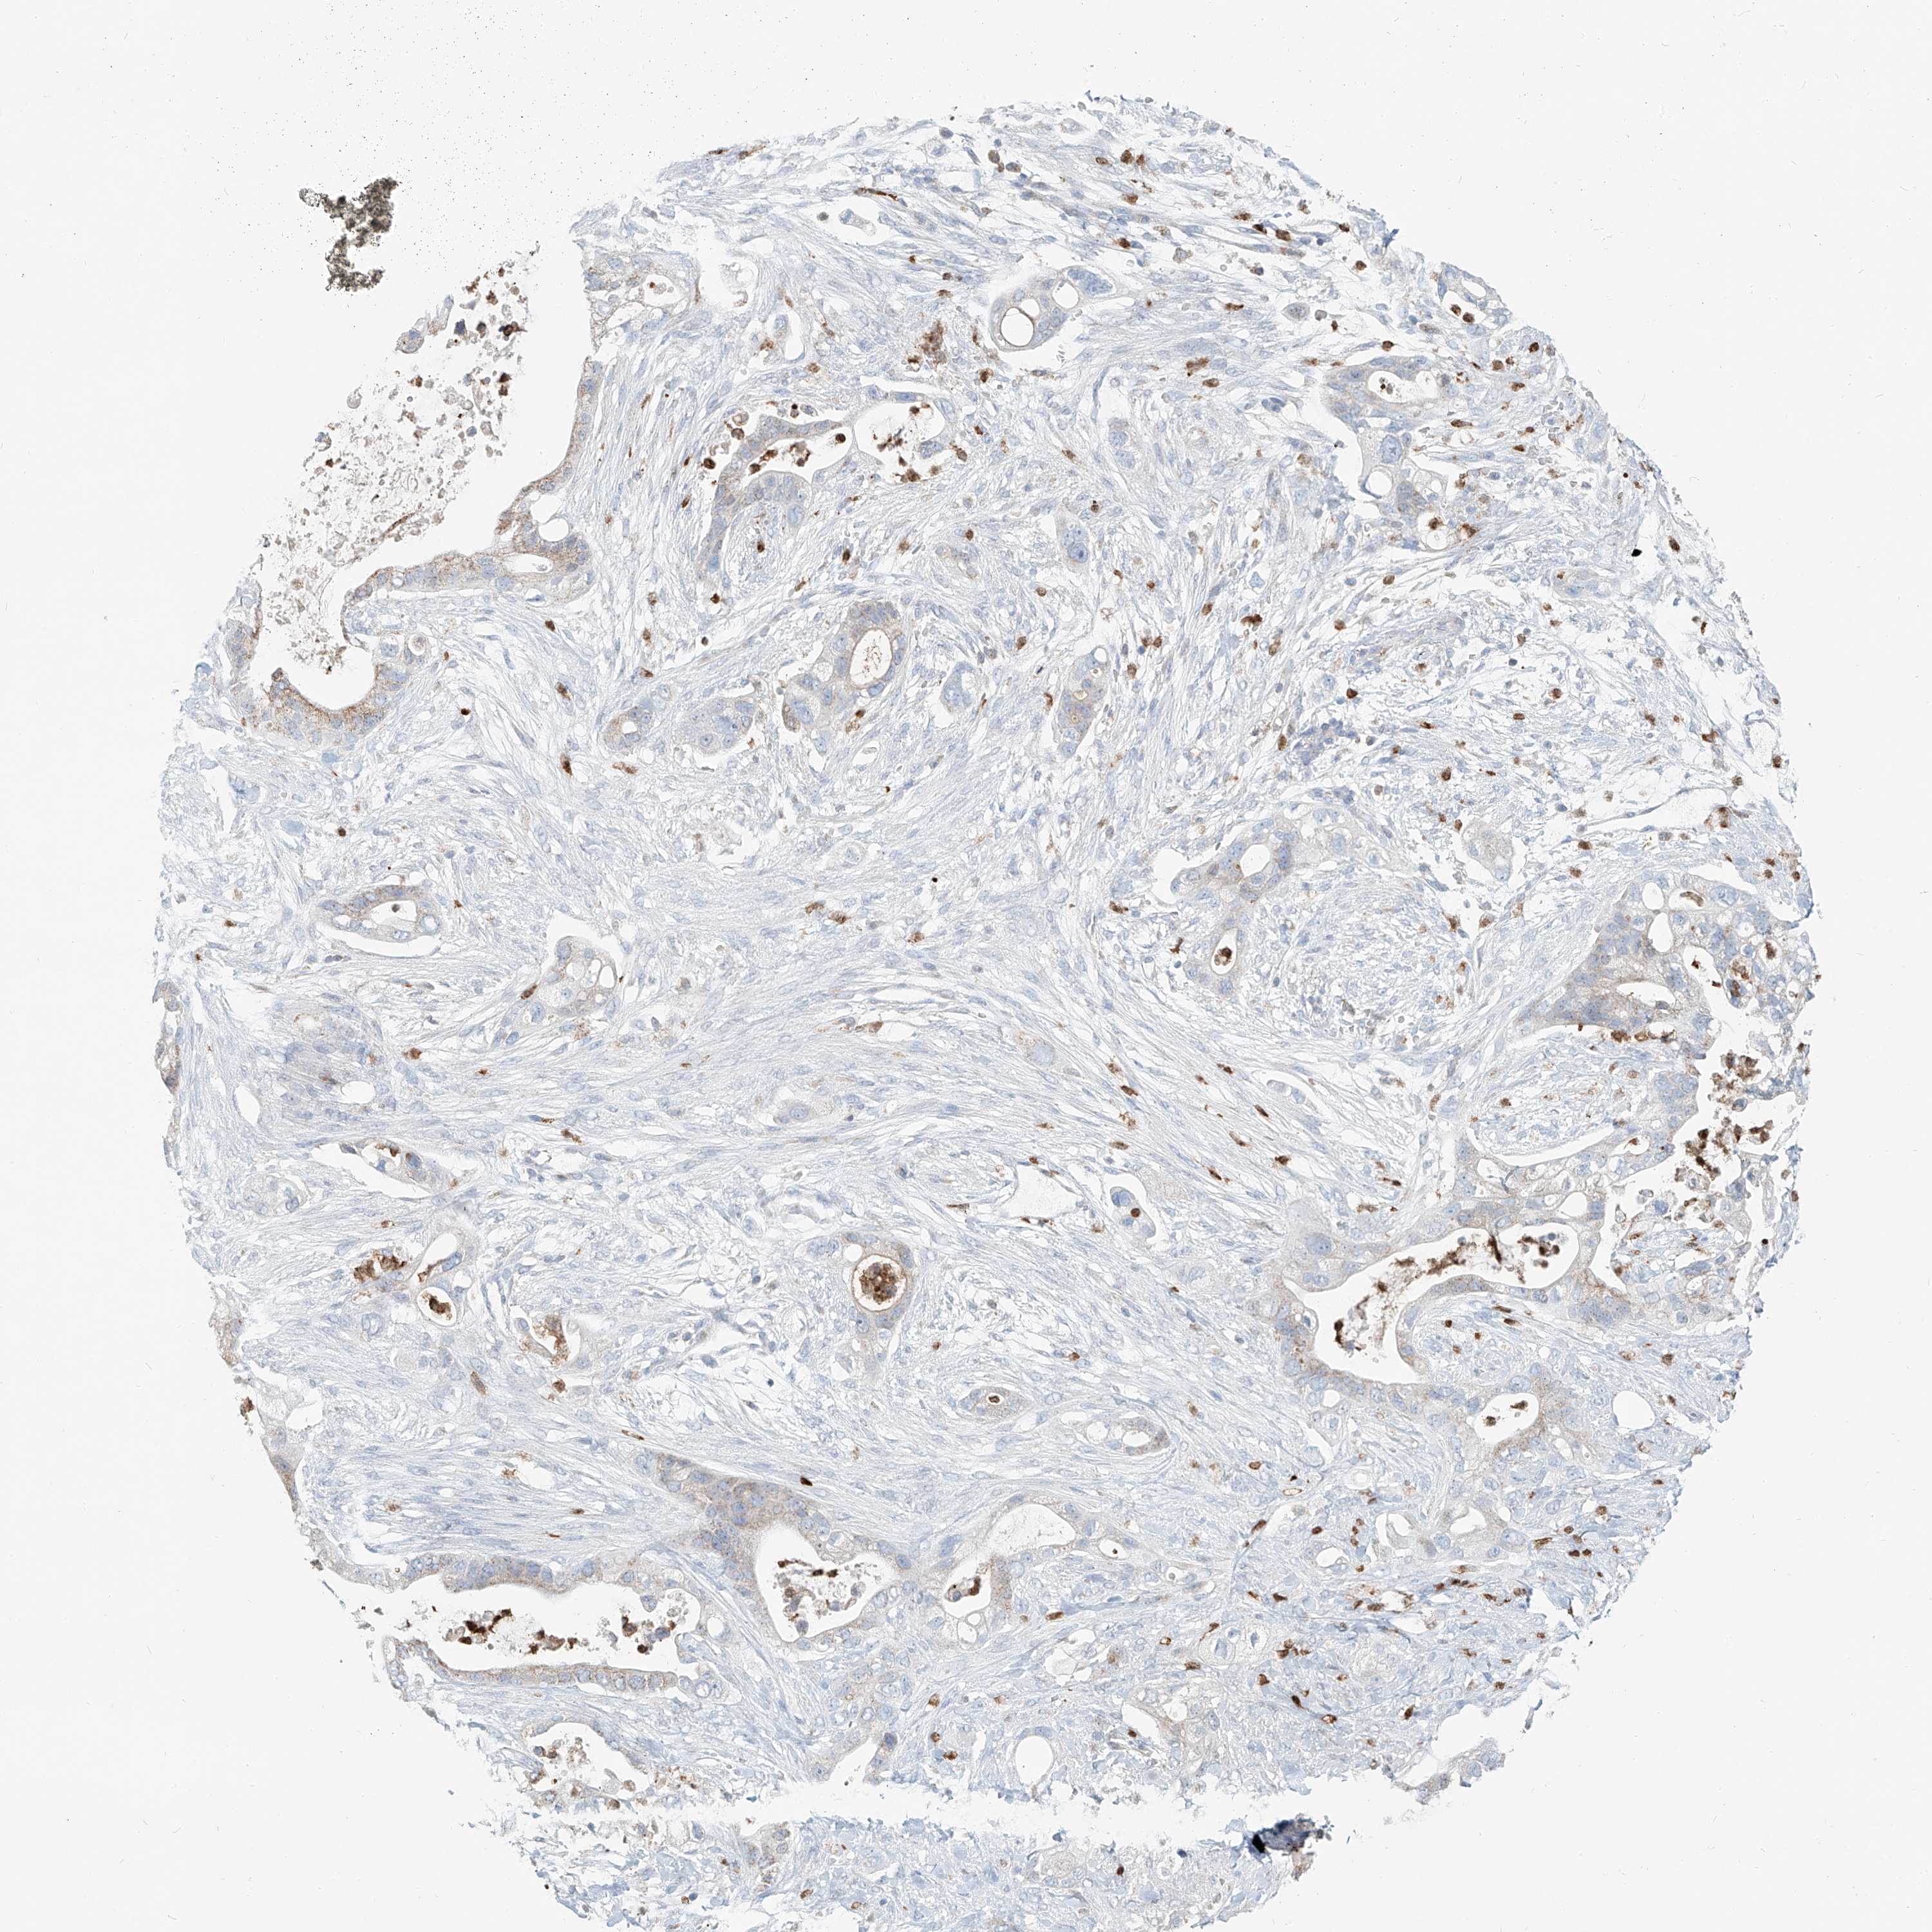

PANCREATIC CANCER - Protein expressioni

A mouse-over function shows sample information and annotation data. Click on an image to view it in a full screen mode. Samples can be filtered based on level of antibody staining by selecting one or several of the following categories: high, medium, low and not detected. The assay and annotation is described here.

Note that samples used for immunohistochemistry by the Human Protein Atlas do not correspond to samples in the TCGA dataset.

Antibody stainingi

Antibody staining in the annotated cell types in the current human tissue is reported as not detected, low, medium, or high, based on conventional immunohistochemistry profiling in selected tissues. This score is based on the combination of the staining intensity and fraction of stained cells.

Each image is clickable and will lead to virtual microscopy that enables deeper exploration of all samples and also displays staining intensity scores, fraction scores and subcellular localization as well as patient and tissue information for each sample.

Antibody HPA029412

Antibody CAB034366

Staining

High

Medium

Low

Not detected

Intensity

Strong

Moderate

Weak

Negative

Quantity

>75%

75%-25%

<25%

None

Location

Nuclear

Cytoplasmic/membranous

Cytoplasmic/membranous,nuclear

Adenocarcinoma, NOS